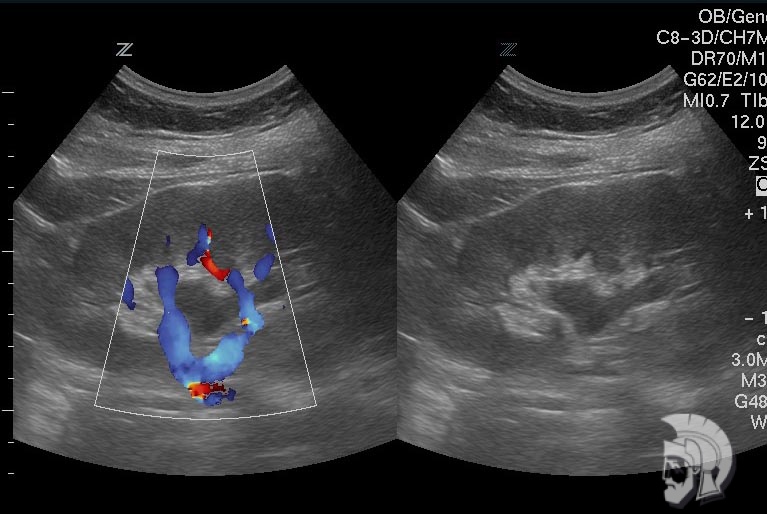

Фото почки.

Умеренное расширение почечной лоханки левой почки у подростка 16 лет с хроническим левосторонним пиелонефритом. Исследование в режиме цветового допплеровского картирования |